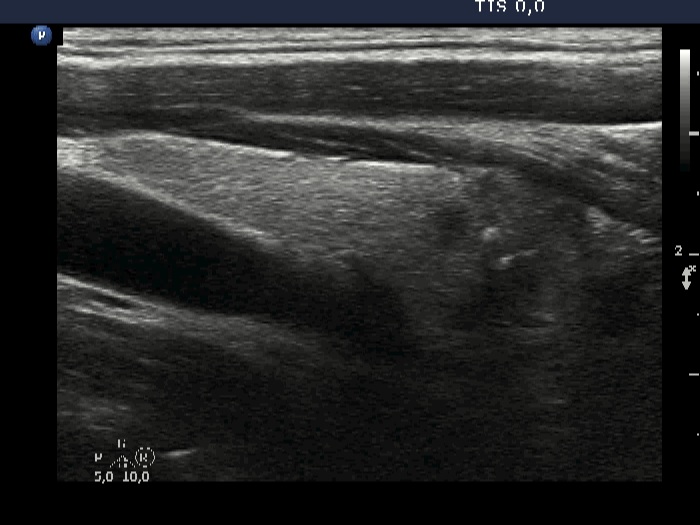

There was a lymph node 3 cm-s above the upper pole of the right thyroid lobe. The node has broad hilum.